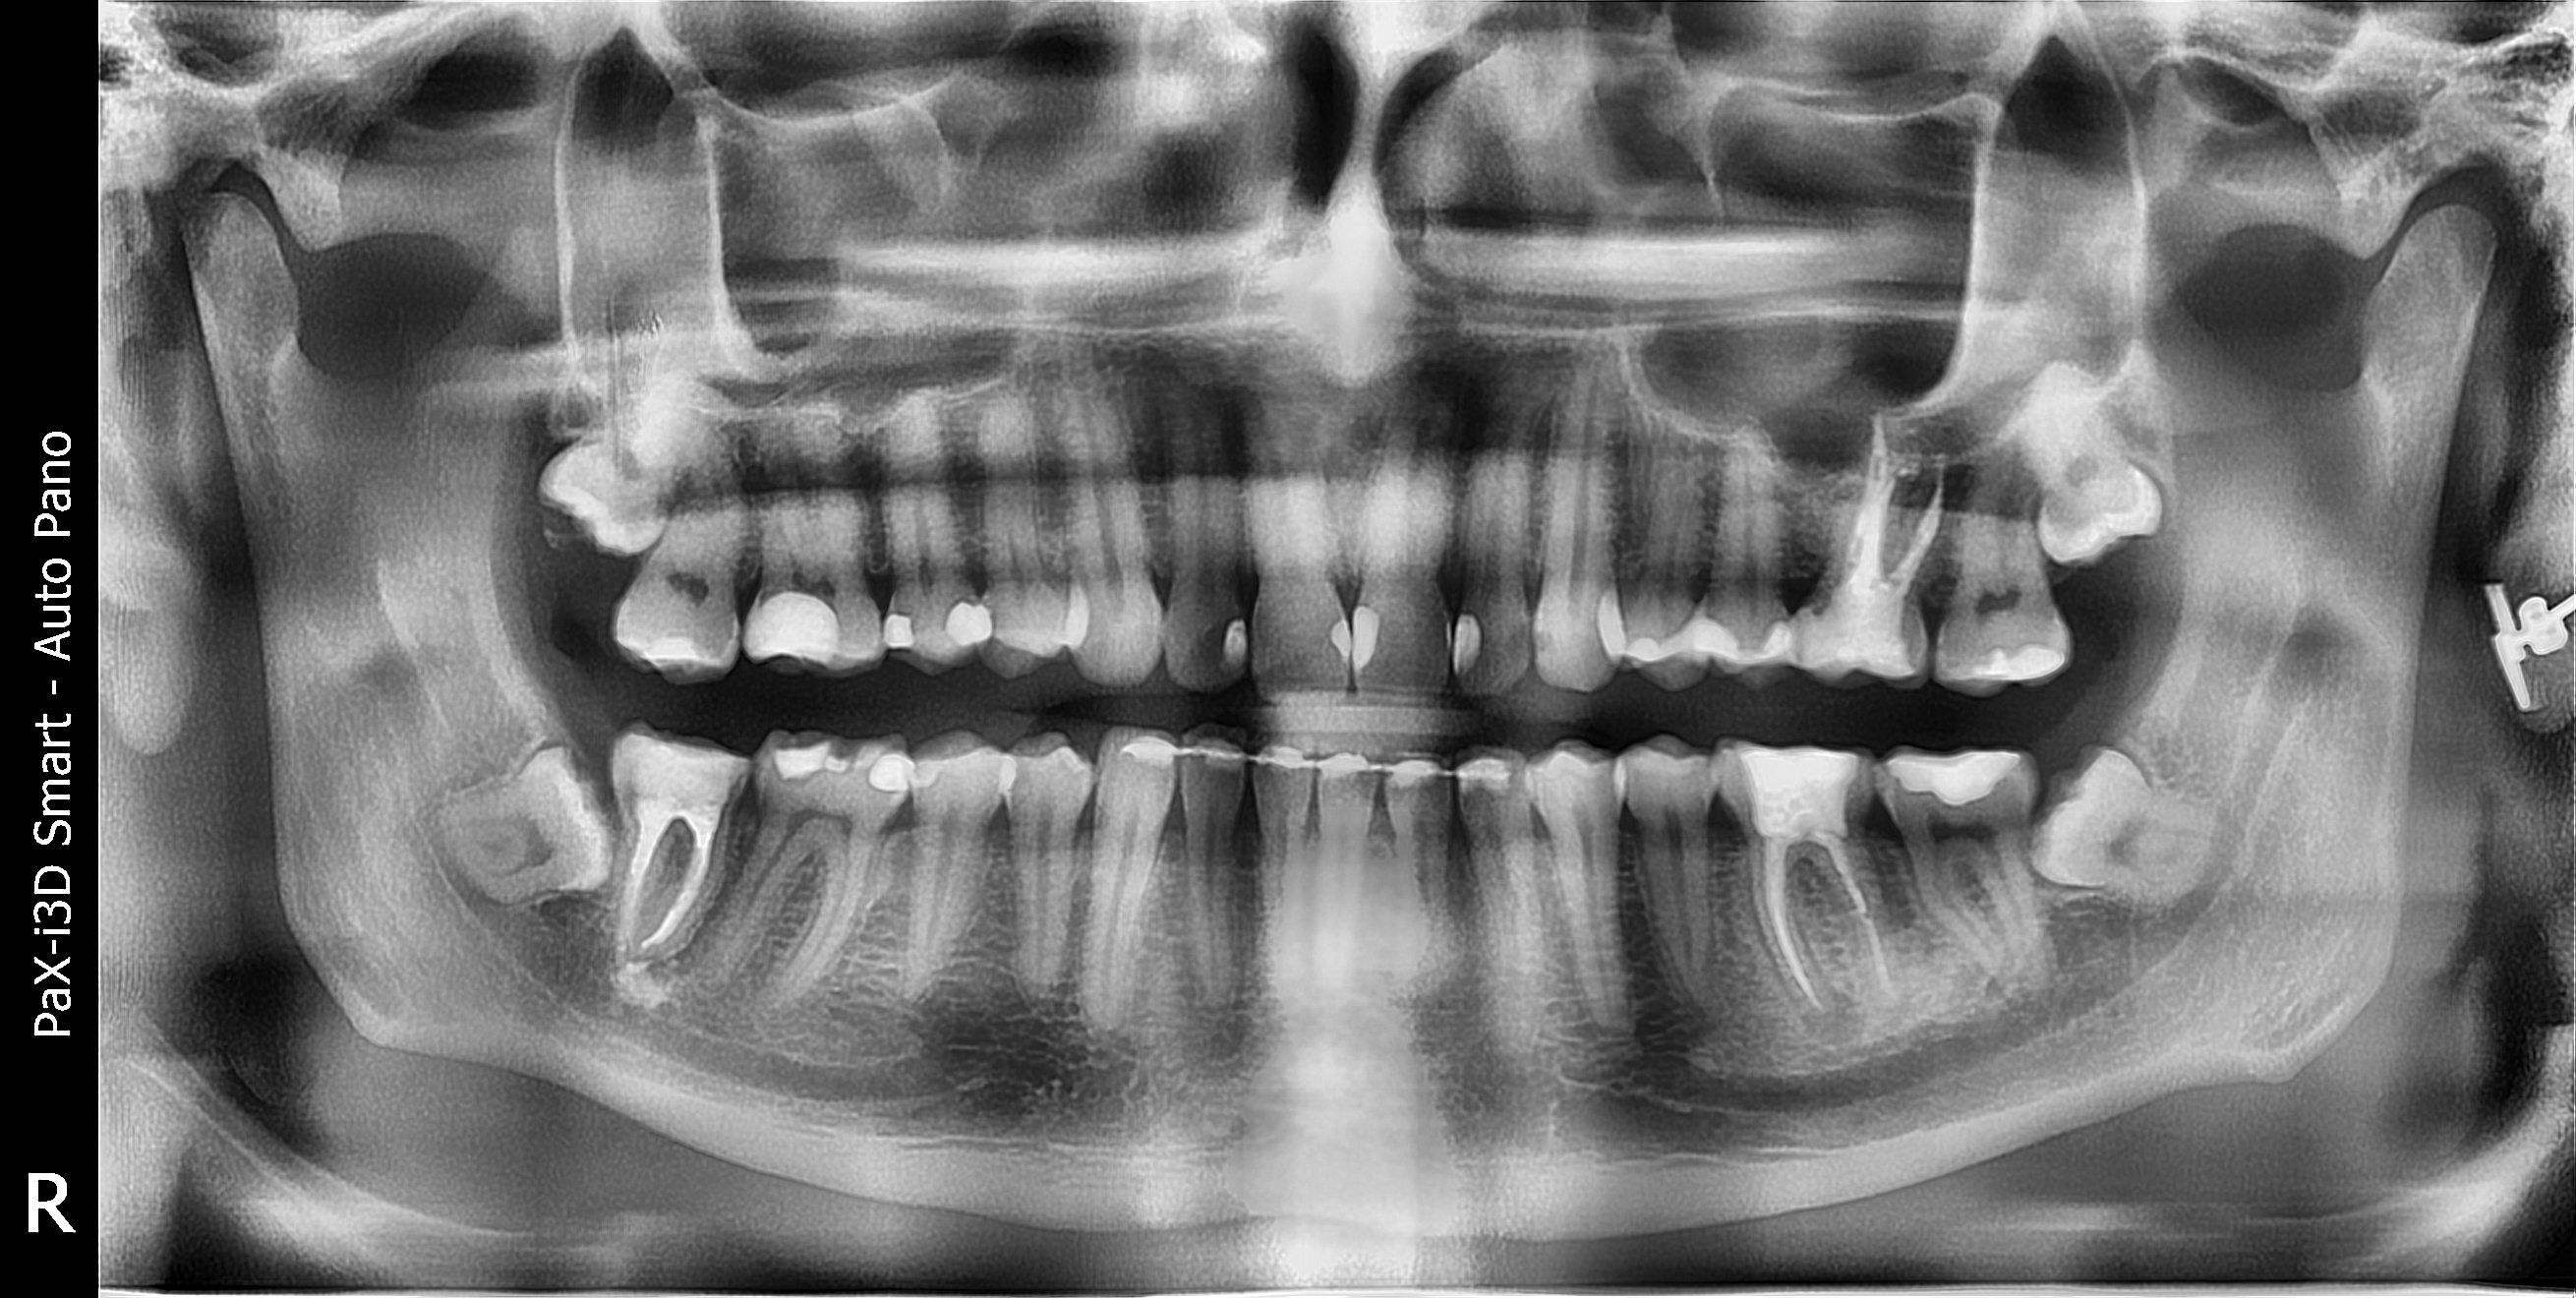

«У нас кожен випадок обов’язково супроводжується діагностикою – ми робимо КТ, оцінюємо положення зуба, його контакт із нервом, стан сусідніх зубів. Якщо є ризики – діємо на випередження. Якщо все в нормі – спостерігаємо в динаміці. Але ключове – не ігнорувати перші сигнали організму», – зазначив хірург-стоматолог Тарас Кунанець.

Центр стоматології Bioclinic оснащений усім необхідним сучасним обладнанням: комп’ютерним томографом, мікроскопом, сканером, лазером хірургічним, п’єзотом, цифровим аксіографом ModJaw тощо, яке допоможе у діагностиці і проведенні процедур.